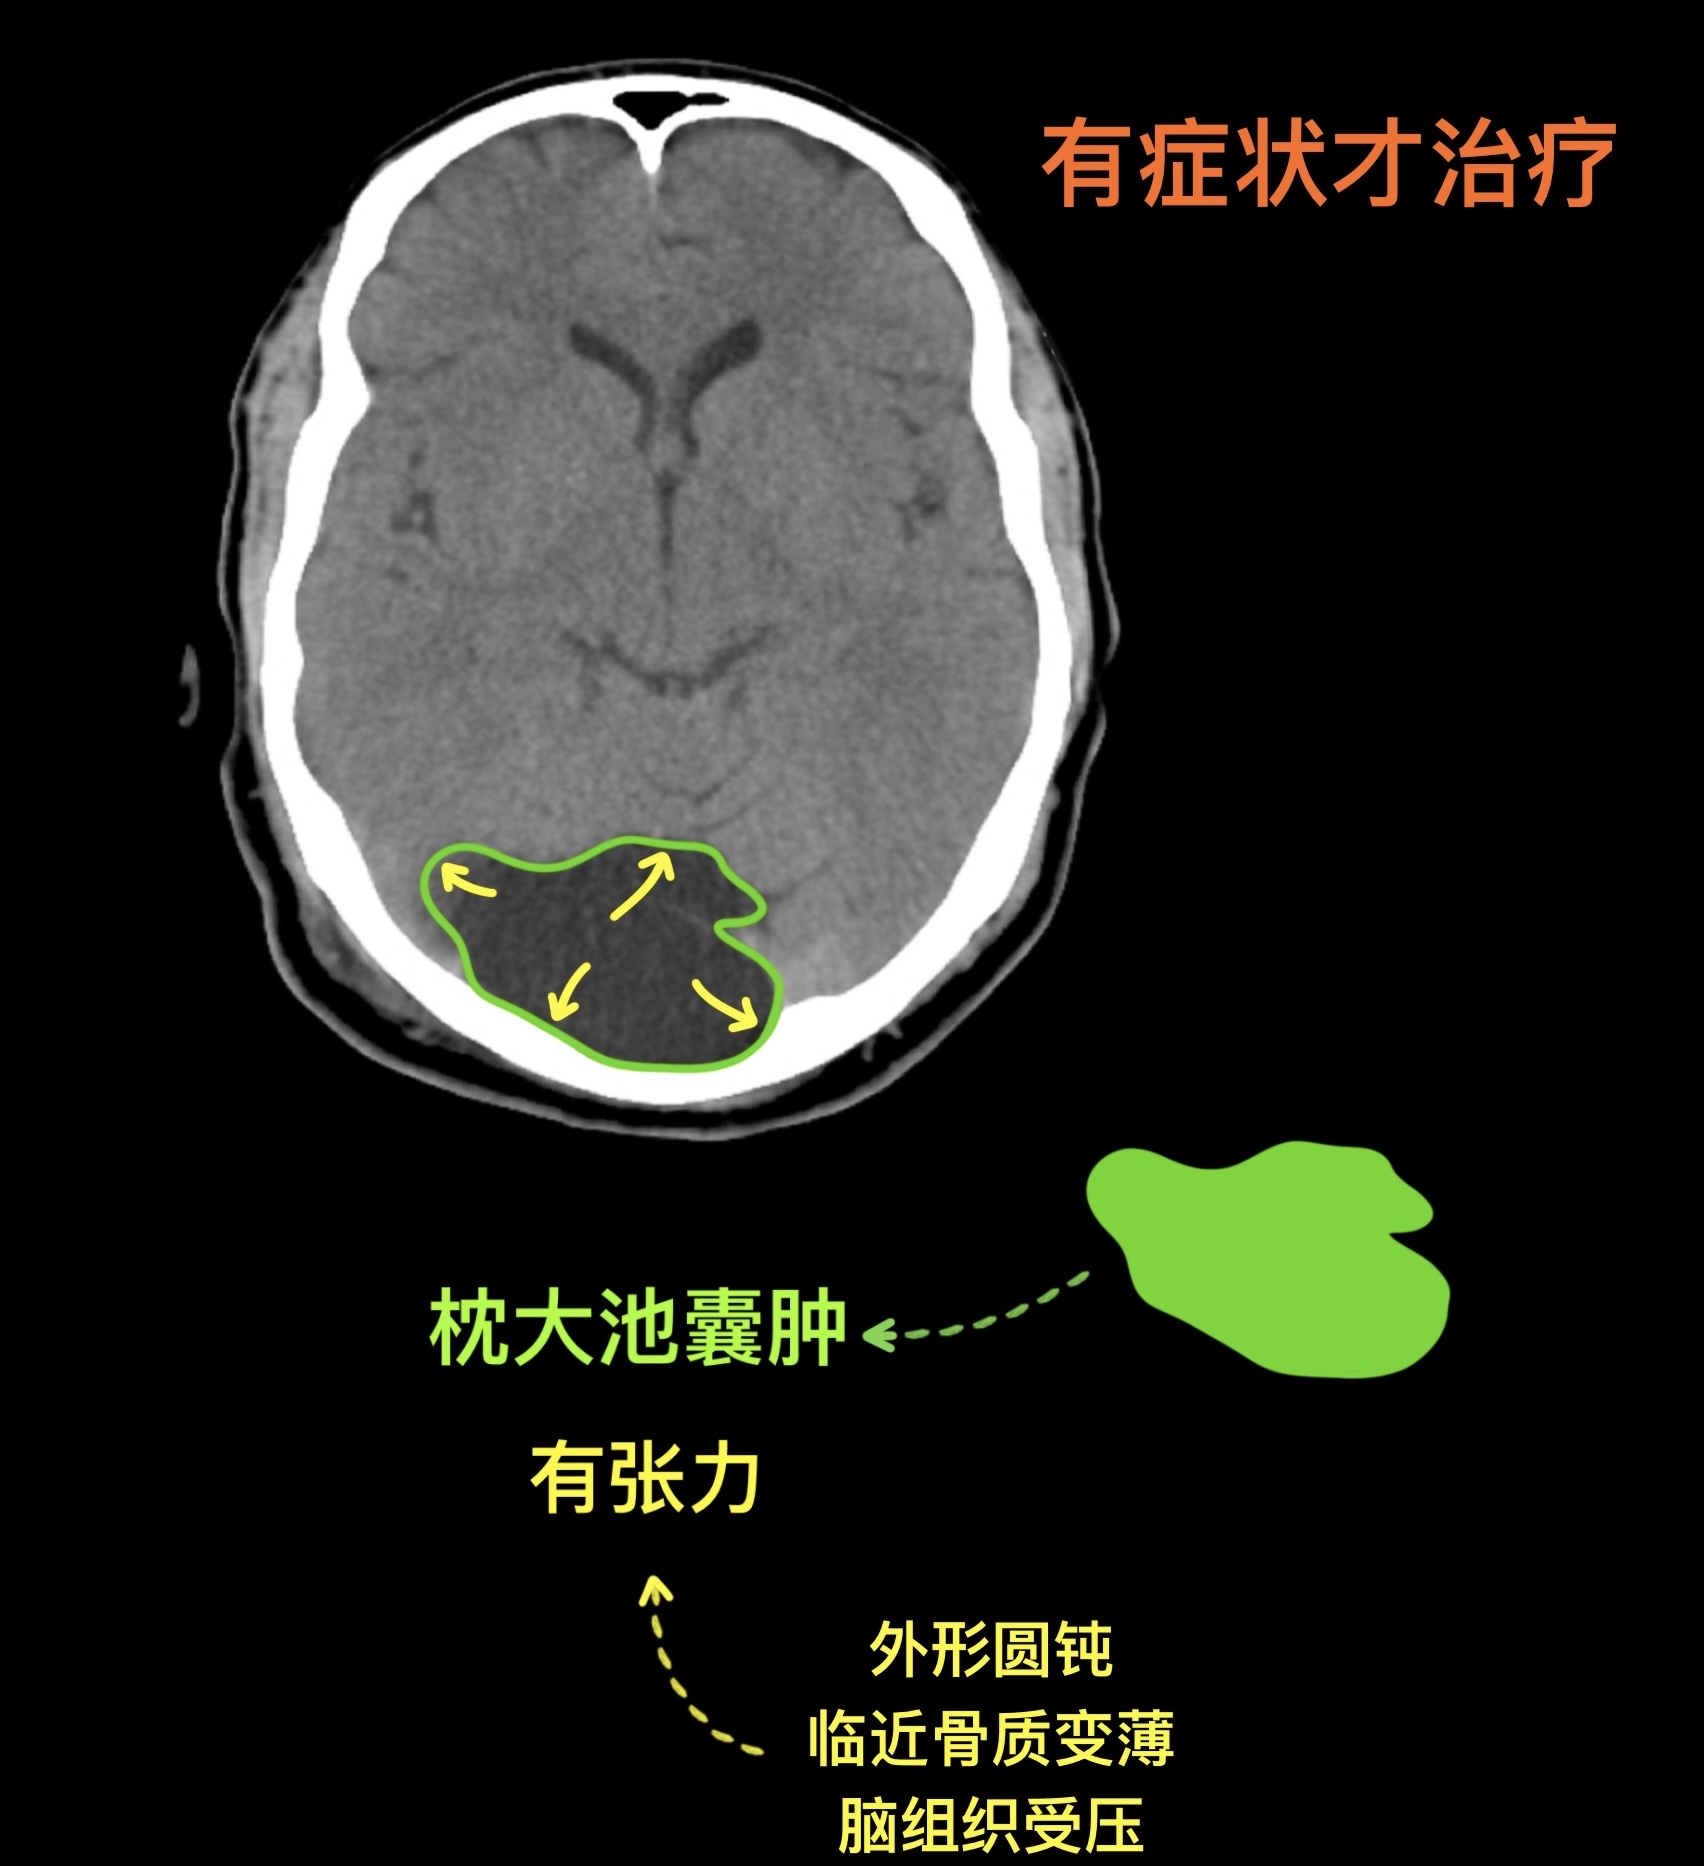

枕大池囊肿

枕大池蛛网膜囊肿